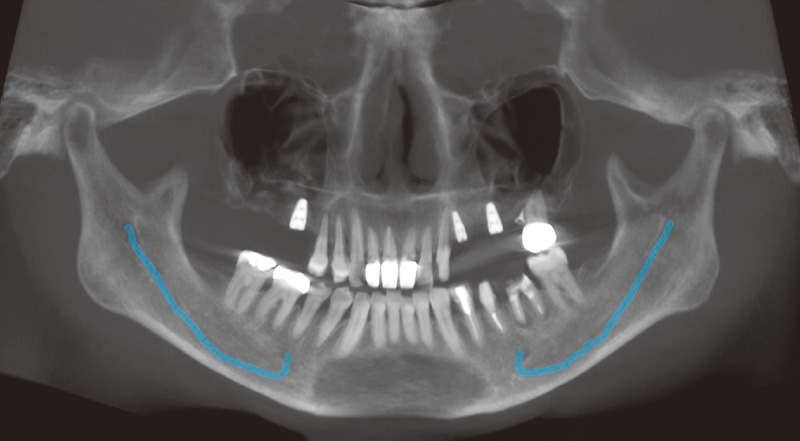

図4 インプラント埋入後の状態 -